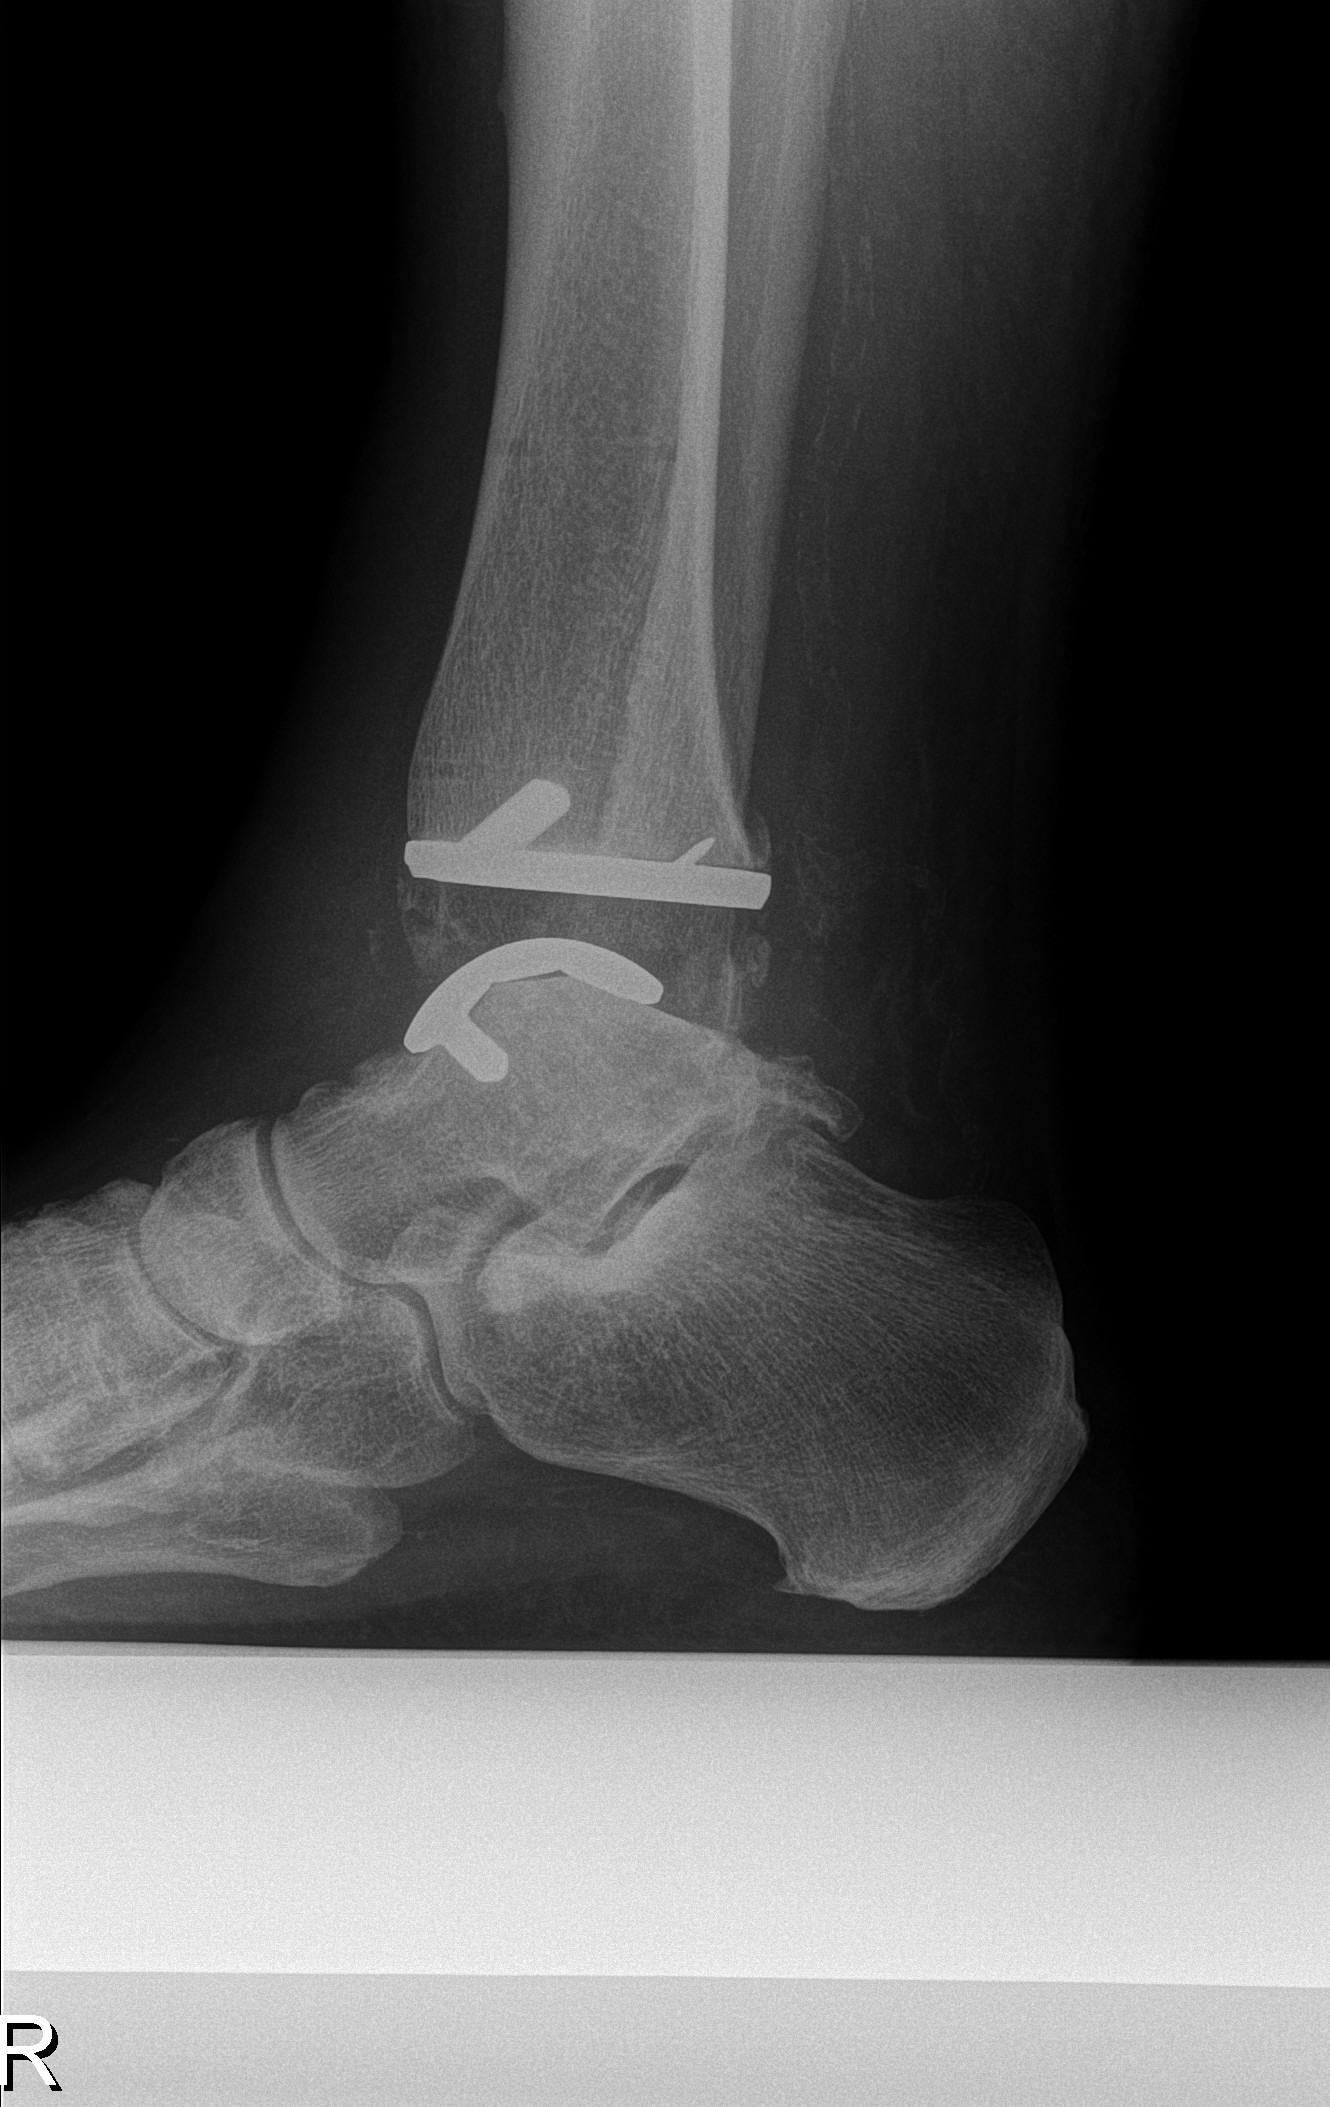

In AZ Turnhout plaatsen we de Infinity enkelprothese (firma Stryker). Een dun laagje (2 à 3 mm) ziek kraakbeen en onderliggend bot worden verwijderd, en in de plaats wordt een metalen plaatje tegen het bot geplaatst (metalen prothese component). Tussen de twee metalen plaatjes van de prothese komt een plastieken schijfje (poly-ethyleen liner) dat beweging in het enkelgewricht mogelijk maakt. Indien nodig verricht de chirurg nog bijkomende ingrepen aan je voet of enkel om deze mooi recht te krijgen (aligneren) of beter te doen bewegen (bv. achillespees verlenging).